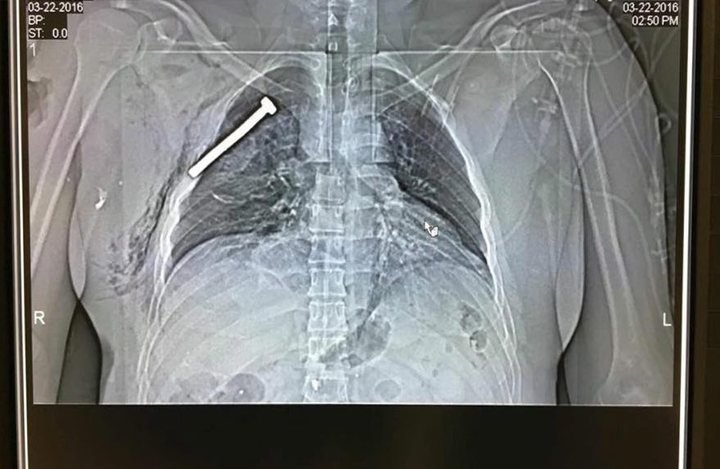

volkskrant twitterde op dinsdag 22-03-2016 om 21:08:28 Live - Spijker te zien op röntgenfoto slachtoffer #Brussel.https://t.co/UIjbE77IOH https://t.co/cnt44CvwpA reageer retweet

[ afbeelding ]

Leuk man, internet. Zelfs je binnenste is niet veilig meer.